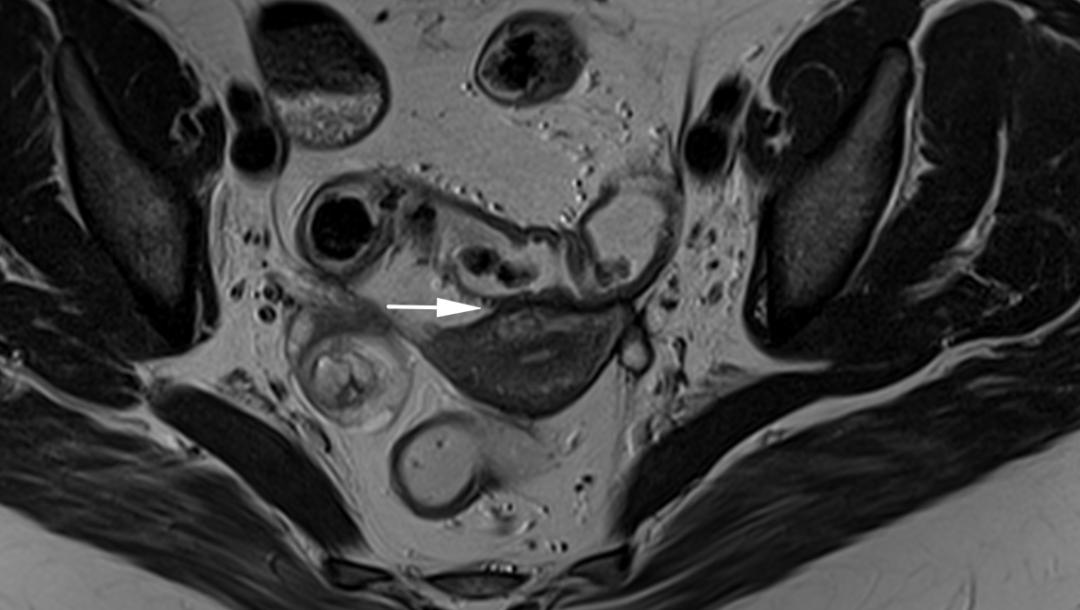

CASE 6

子宫内膜异位至右侧卵巢,T2WI 矢状位呈类圆形高信号,注意的是同时异位至道格拉斯窝及宫颈后区,T2WI 矢状位显示病灶呈低信号,中间夹杂更高信号结节,T1WI 轴位显示病灶多发高信号结节(提示多发出血点)